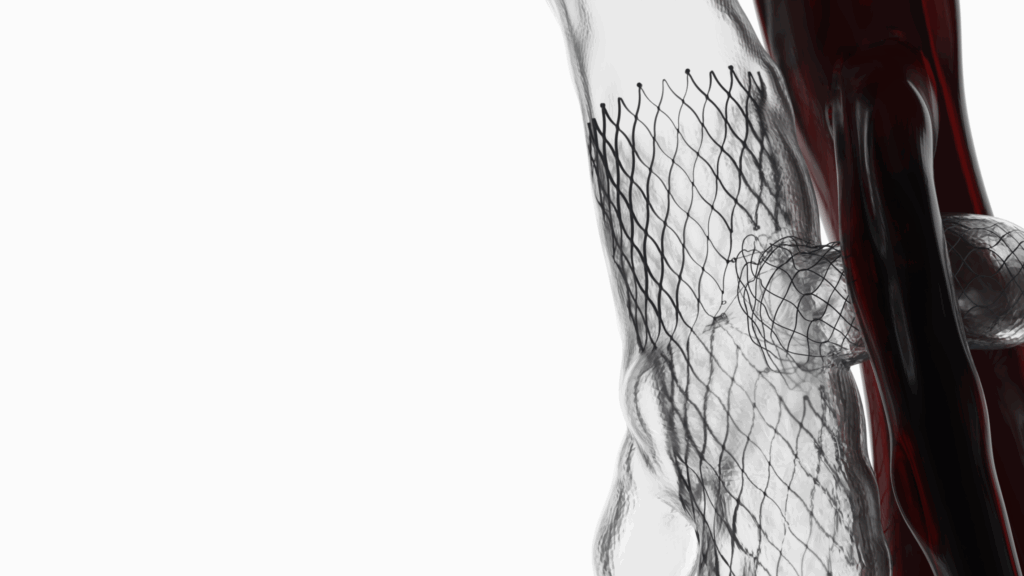

UNE SOLUTION ADAPTÉE : LE T-STENT VEINEUX

L’objectif : restaurer la circulation naturelle tout en préservant l’intégrité de la veine. Le T-Stent Veineux développé par ID NEST Medical répond précisément à ces défis. Conçu pour épouser les structures veineuses souples et dynamiques, il offre :

UNE ARCHITECTURE ANATOMIQUE

La structure du T-Stent veineux est composée de stents indépendants capables de s’adapter aux variations de la veine rénale. Cette modularité garantit une apposition homogène sur la paroi, même en cas de compression sévère, et limite les risques de déformation.

UNE CONNEXION ÉLASTIQUE BREVETÉE

Les modules sont reliés par une connexion élastique qui absorbe les mouvements naturels de l’abdomen. Ce mécanisme réduit les contraintes exercées sur la veine et assure une stabilité compatible avec les variations de pression propres au Nutcracker.

UNE STABILITÉ RENFORCÉE

Le design du T-Stent offre un ancrage fiable dans une zone anatomique très mobile. Cette stabilité annule le risque de migration, un enjeu majeur dans la prise en charge du Nutcracker Syndrome.

PRINCIPE DE FONCTIONNEMENT

Le T-Stent veineux a été conçu pour restaurer le flux sanguin dans la veine rénale comprimée, cœur du Nutcracker Syndrome. Grâce à son architecture modulaire et à ses connexions élastiques, il s’adapte à la morphologie de la veine tout en absorbant les mouvements naturels de l’abdomen. Une fois positionné dans la zone de compression, il crée un canal stable et homogène qui empêche l’écrasement de la veine par les structures environnantes.

Cette stabilité mécanique permet de réduire la pression intraveineuse, de rétablir une circulation fluide et de soulager durablement les symptômes, sans provoquer de protrusion ou de surdilatation.